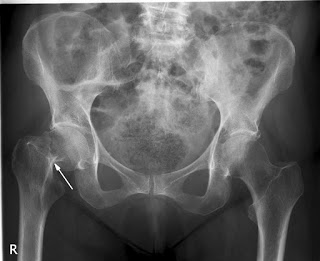

En pacientes con fractura de cadera, la cirugía en las primeras seis horas del diagnóstico no obtuvo mejores resultados que la realizada a las 24 hs del mismo. The Lancet, 29 de febrero de 2020.